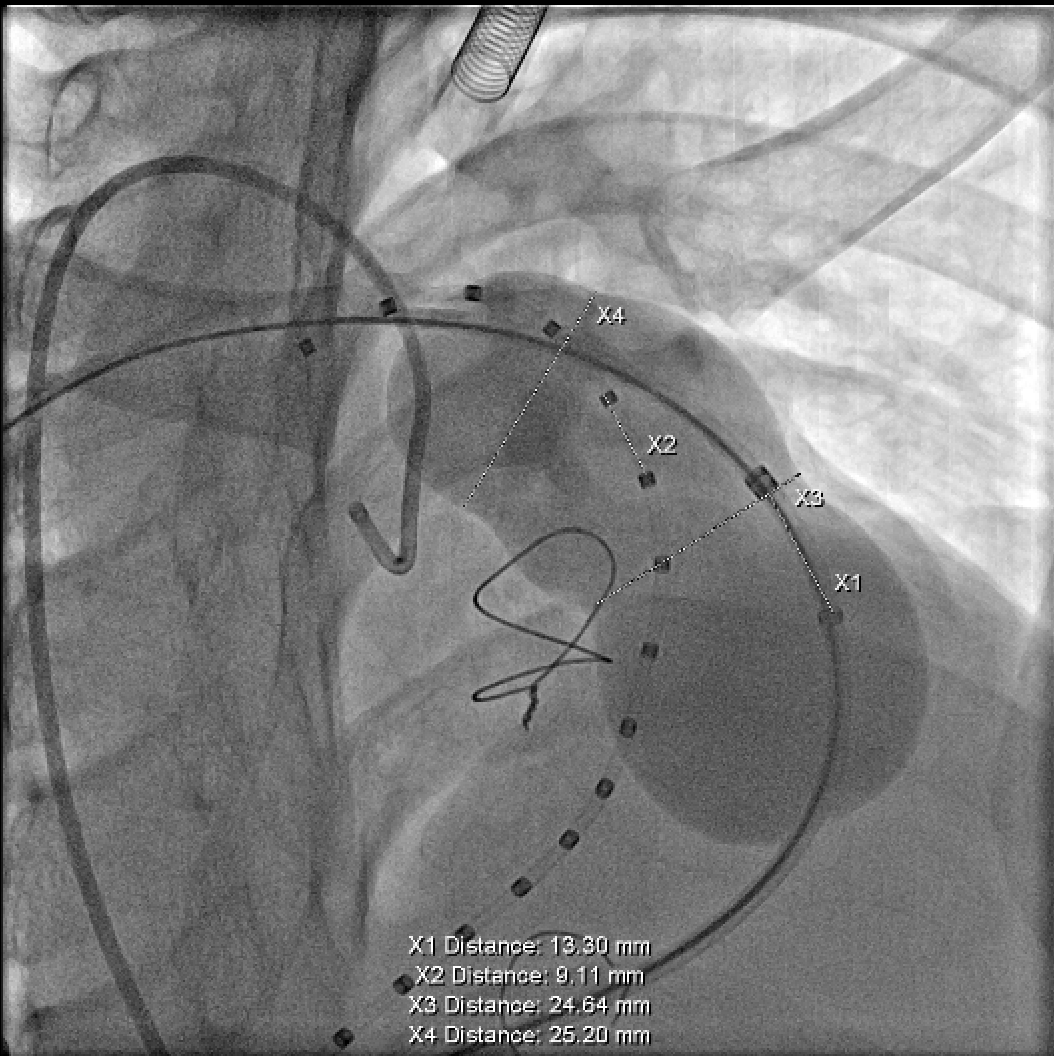

肺动脉造影测量肺动脉内径等参数:

使用顺应性球囊测量肺动脉内径等参数: